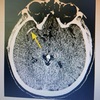

50 anos, hemiparesia esquerda. Qual Diagnóstico?

AVCi Oclusão da artéria cerebral média direita